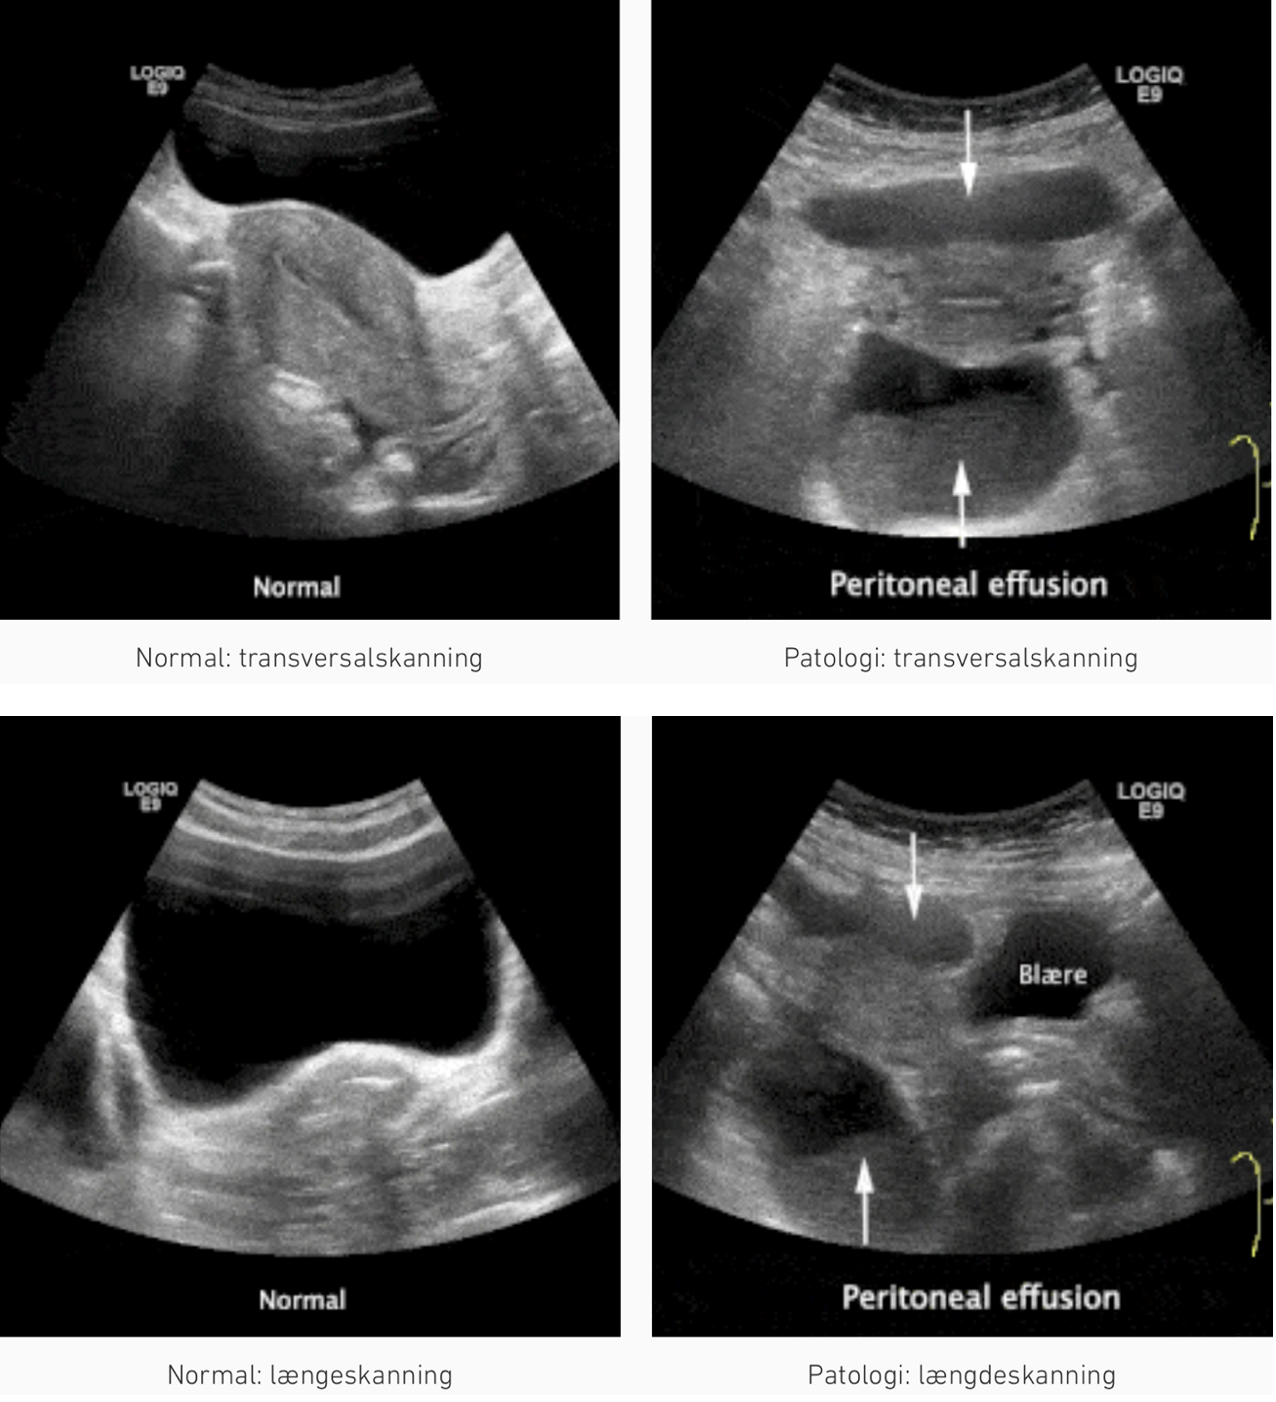

B. Hø. øvre kvadrant i midt aksillærlinjen: peritonealansamling i: fossa hepatorenale (Morison’s pouch) + perihepatisk

B. Ve. øvre kvadrant i bageste aksillærlinje: peritonealansamling i: fossa splenorenale + perisplenisk

Zone 6 (Pelvis position over symfysen): ansamling i: fossa Douglasi (kvinder) / fossa rectovesicale (mænd)